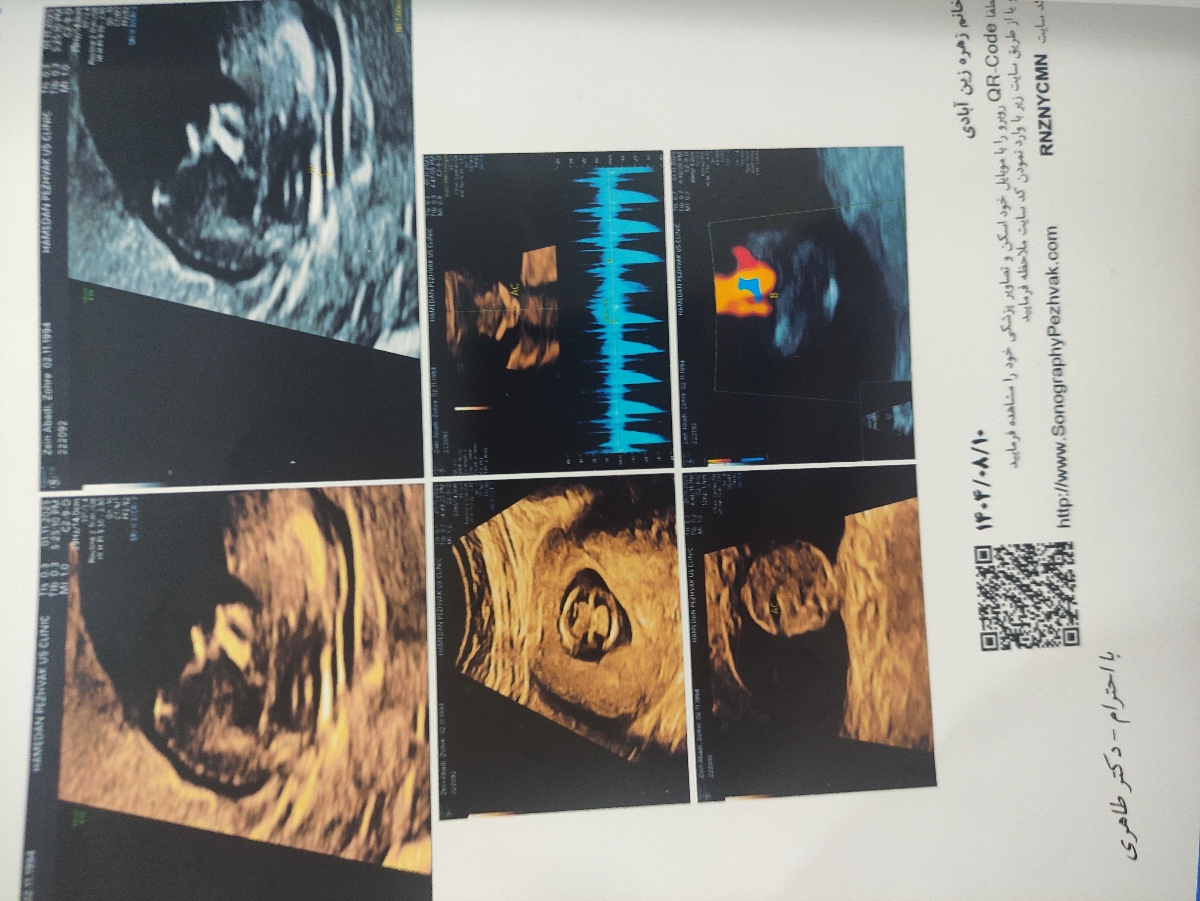

دوستان به نظرتون جنسیت چی هست🤔؟؟؟

سلام به روی ماهتون مامان جان

خداروشکر همه چیز عالی است و مشکلی ندارد فقط جایگاه جفت مشخص نشده است و جهت تفسیر صحیح باید منتظر بخش خون غربالگری باشیم ❤️